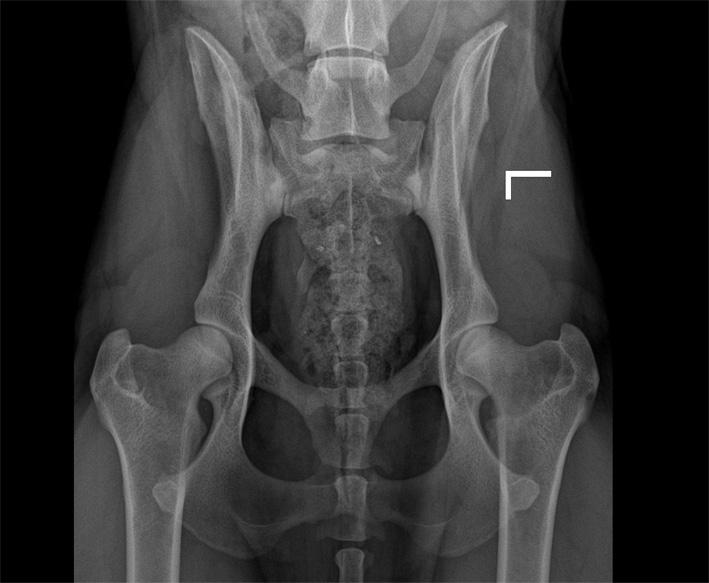

![]() HD-D/ HD-mittel/ HD 3 |

| HD:E/HD-schwer/HD 4-5 |

D |

= Grad2 (mittelgradig) |

HD-3 |

mittel |

Gravierende Veränderungen mit arthrotischen Zubildungen, NORBERG-Winkel zwischen 90 und 100 Grad |

E/1 |

= Grad3 (schwer) |

HD-4 |

schwer |

Das gesamte Gelenk ist stark verändert, evtl. eine vollständige Luxierung, NORBERG-Winkel unter 90 Grad |